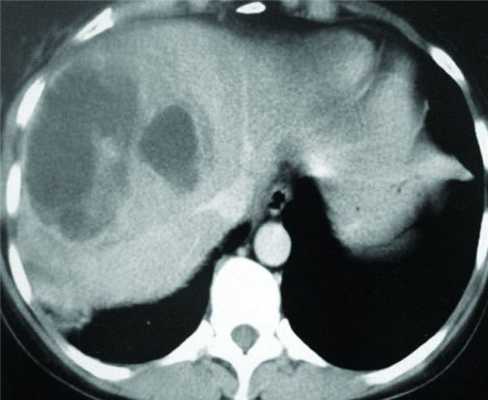

КТ диагностика тубоовариального абсцесса: Подходы и изображения

Раздел: Объективный взгляд